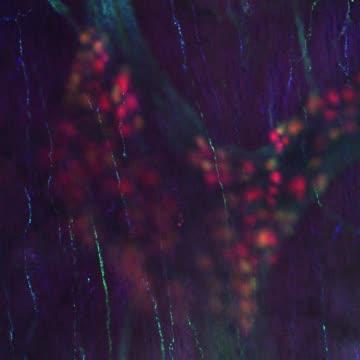

video: Video showing a three-dimensional view of the enteric nervous system.

Philadelphia, February 27, 2020 - In a groundbreaking discovery, researchers at Children's Hospital of Philadelphia (CHOP) developed a new imaging method that allows scientists to view the enteric nervous system (ENS) - a key part of the human colon - in three dimensions by making other colon cells that normally block it invisible. The ENS has previously only been visible in thin tissue slices that provide limited clinical information. The findings were published online today in the journal Gastroenterology.

Using mouse and human colon tissues, the study team developed an imaging method that combined several techniques, including tissue and cell staining, the use of pinhole microscopes and quantitative analysis to characterize the cells of the colon in three dimensions. By not sectioning tissue, this new approach preserves the associations with other bowel cells in three-dimensional space. This is important in assessing bowel motility, which requires many cell types to work together to coordinate muscle contration and relaxation.

In total, the study team created 280 confocal Z-stacks - the process that allows them to render the images in three dimensions - and was able to acquire quantitative data from 14 adult human colons. Additionally, they were able to visualize the ENS in children with Hirschsprung disease.